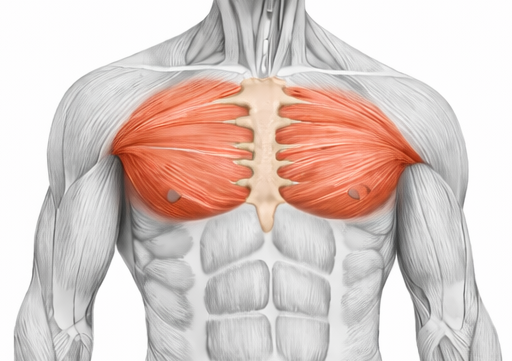

Thoracic Region

Learn Gross Anatomy of Thoracic Region including functional aspects, joints, nerves, vessels, and its clinical aspects..